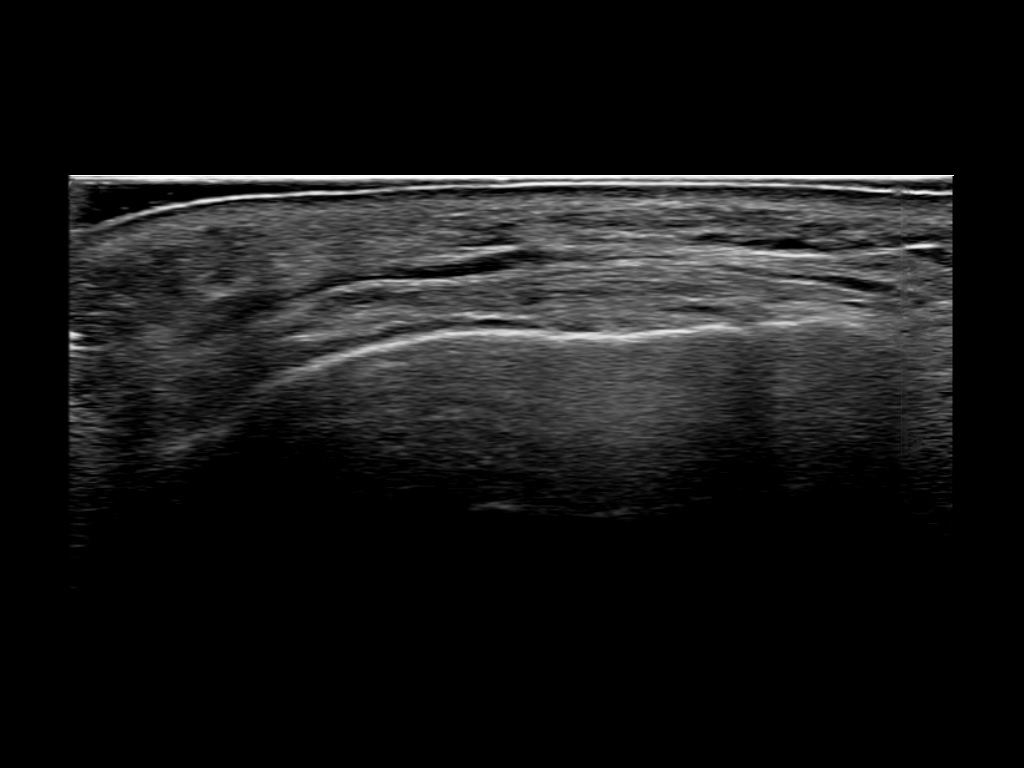

Filler deposits may end up unintentionally in the SMAS or fascial layers of the skin. Very often this will not lead to adverse events, however, adverse events ( nodules, migration / redistribution impaired muscle movement and smiling and malar edema) are are often related to filler ending up in the SMAS or fascia.

Study the first image to recognize the different layers. If you are sure about the layers, swipe to the second image to view the answer (if applicable).